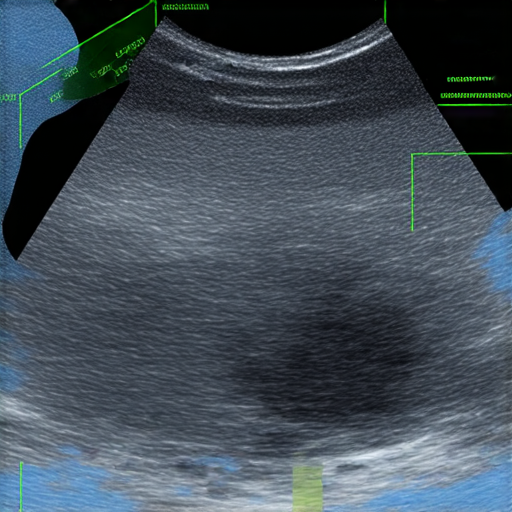

盆腔超聲波檢查過程中的醫療設備與檢查結果圖示,展示健康秘密與診斷資訊,讓你了解盆腔健康與疾病預防,提升英語能力,促進健康意識。

盆腔超聲波檢查是一種非侵入性的影像檢查技術,主要用於檢查女性的生殖器官,包括子宮、卵巢及其他相關結構。透過使用聲波,醫生可以清楚看到這些器官的形狀和大小,幫助診斷各種潛在的健康問題。

檢查通常是在醫療機構進行,你需要躺在檢查台上,醫生會將一個潤滑劑塗在腹部,然後使用探頭輕輕滑動以獲取影像。